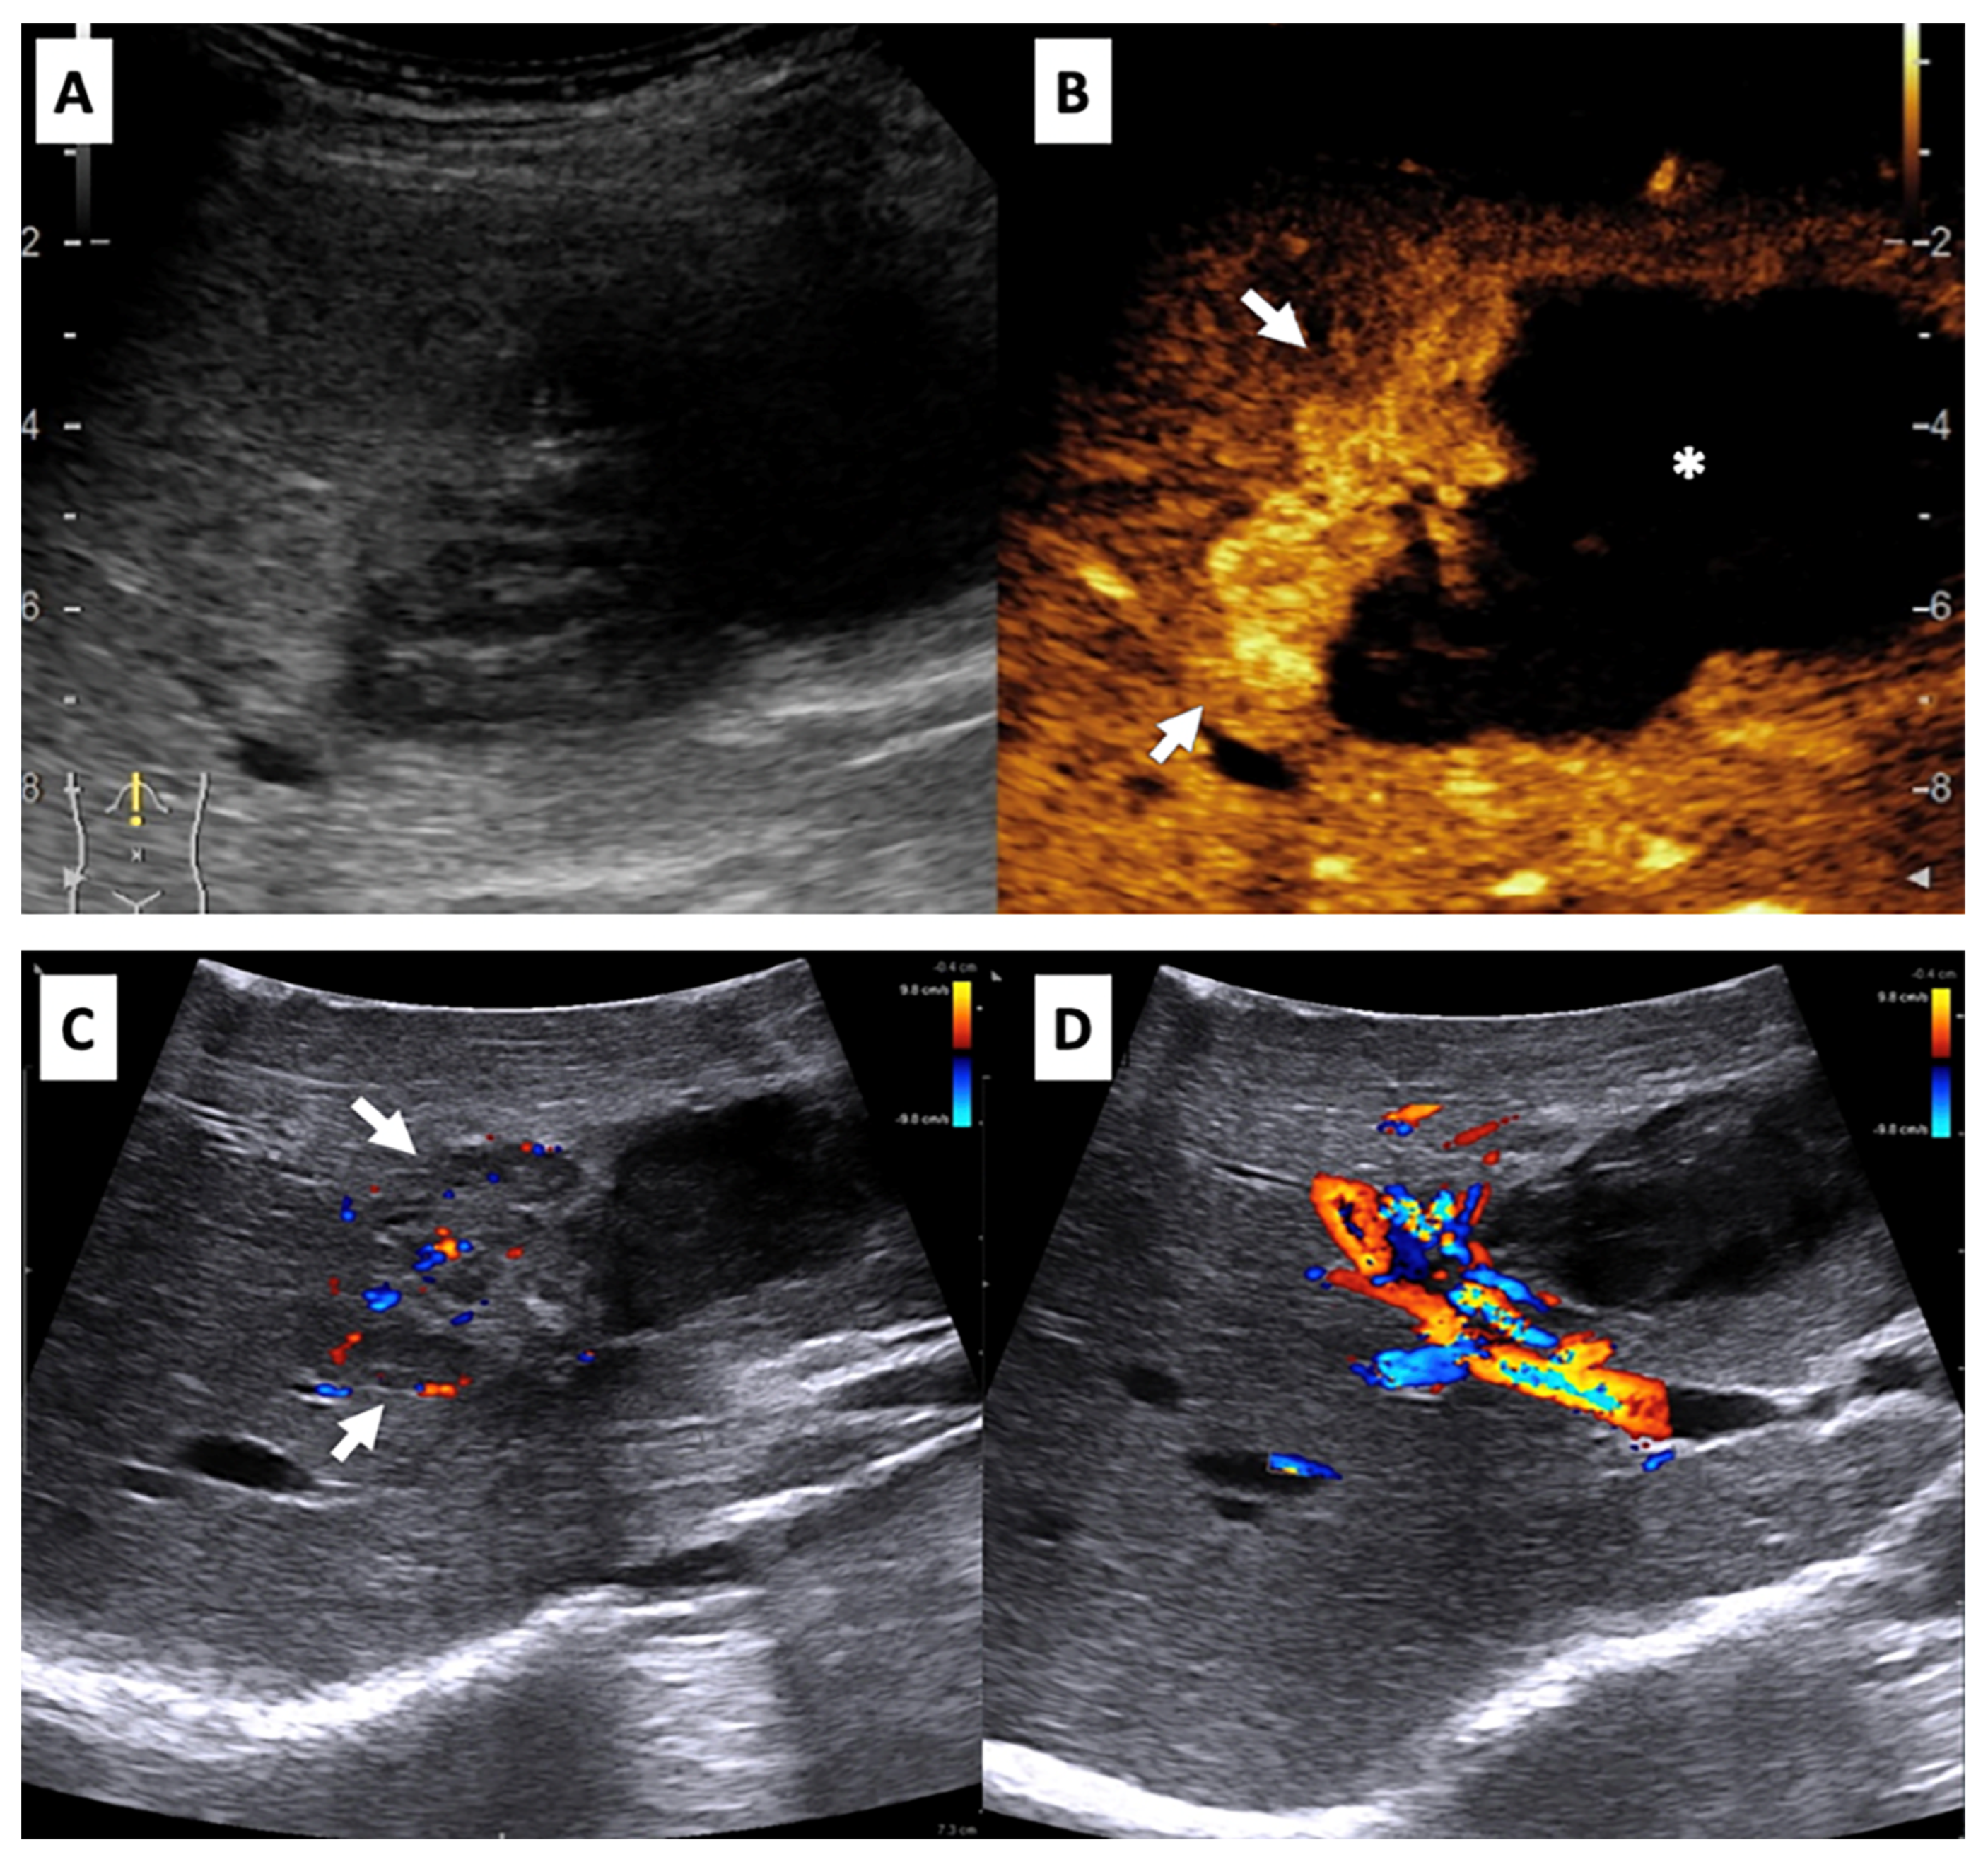

- Matrood, S.; Görg, C.; Safai Zadeh, E.; Alhyari, A. Hepatic perivascular epithelioid cell tumor (PEComa): Contrast-enhanced ultrasound (CEUS) characteristics—A case report and literature review. Clin. J. Gastroenterol. 2023, 16, 444–449. [Google Scholar] [CrossRef] [PubMed]